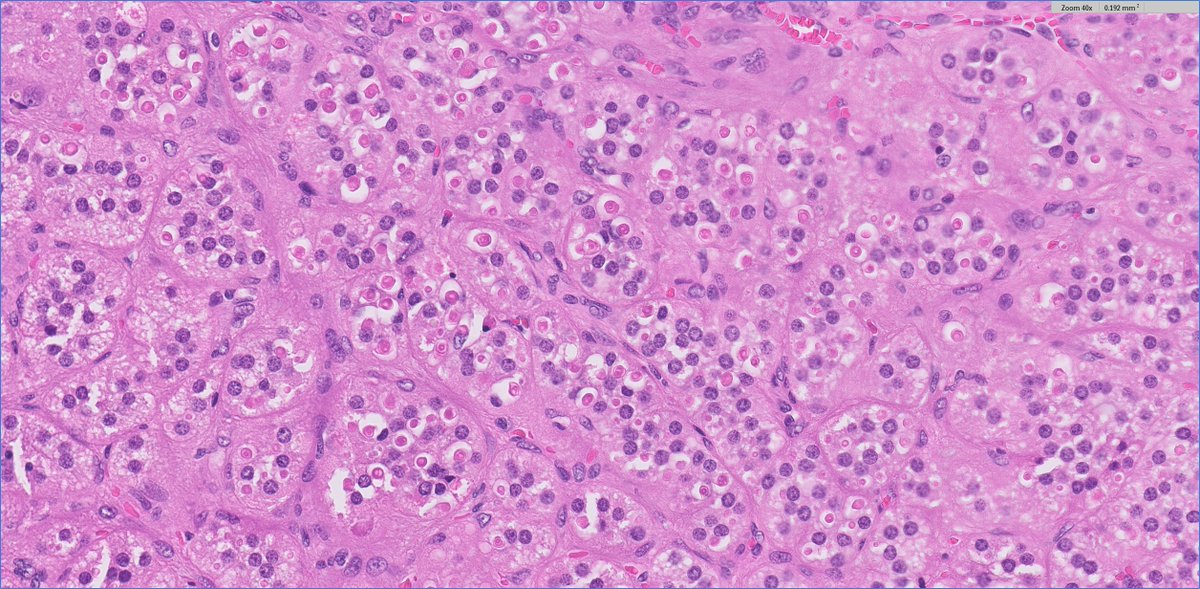

adult M with single adrenal mass, adrenalectomy: 🤔having trouble classifying this oncocytic adrenal neoplasm? 🔑that's b/c it's #endopath#GUpath‼️ 🔬Dx: metastatic prostatic adenocarcinoma (patient had h/o GG5 PCA)

🤔having trouble classifying this oncocytic adrenal neoplasm?

🔑that's b/c it's #endopath⏩#GUpath‼️

🔬Dx: metastatic prostatic adenocarcinoma

(patient had h/o GG5 PCA)